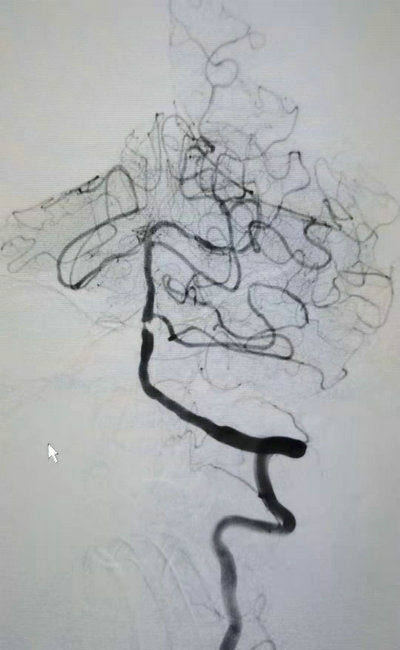

63岁的董先生,因阵发性耳鸣、左下肢无力10天,入住我院神经内科三病区救治。经颅脑MRI检查显示左侧颞枕叶、双侧小脑半球急性脑梗死,给予双联抗血小板聚集、强化他汀、改善循环等对症治疗基础上,又行全脑血管造影,发现患者的基底动脉近端狭窄严重,大于90%,近于闭塞。基底动脉至关重要,若不及时解除病变,随时可能再次出现脑干和(或)小脑梗死,导致呼吸循环功能衰竭,危及生命。由于基底动脉穿支众多,支架植入时挤压斑块可能导致穿支血管堵塞,在所有血管内支架手术中难度最高,风险最大。在与家属充分沟通后,同意实施基底动脉重度狭窄支架植入术。

基底动脉造影